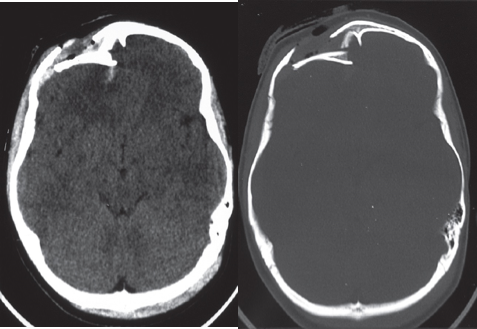

Depressed fracture. Axial unenhanced CT on (a) brain and (b) bone window settings. The depressed fracture and bone fragments are more clearly seen on the bone window settings. Such fractures may require surgical elevation.